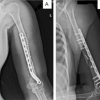

We present the case of a 16-year-old male who suffered a hypersupination injury while playing rugby. He attended his local orthopedic center where he reported pain and limited movement in his right wrist. On examination, he had swelling and diffuse tenderness of his right wrist, with restricted supination and pronation. Examination of his ipsilateral elbow and shoulder was normal and he was neurovascularly intact. Initial plain film radiographs of his right wrist showed a volar dislocation of the right distal radioulnar joint with associated ulnar styloid fracture (Fig. 1). CR was attempted at the time but failed (Fig. 2). He was then referred to our tertiary orthopedic unit.

On arrival to our unit, he underwent computed tomography (CT) scan before the theater (Fig. 3). He subsequently underwent CR under general anaesthetic (Fig. 4). An above elbow (AE) cast was applied postoperatively. He was seen 4 weeks postoperatively in an outpatient’s clinic. He had no tenderness on the exam and was placed into a futura splint. Subsequent radiographs were all in the joint. He was referred to physiotherapy to commence a range of motion exercises and to wean from his splint over the following 2 weeks. He had returned to normal function at 3 months post-injury. His DASH score at 41 at 11 months.